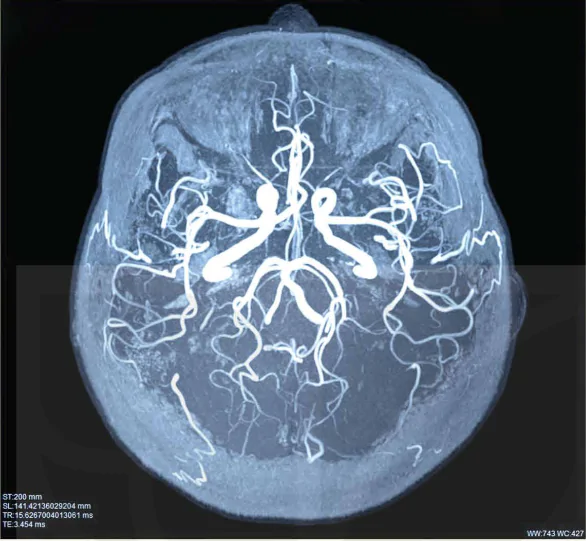

2. Giải thích lí do tại sao khi chụp não thì chụp cắt lớp lại thích hợp hơn X–quang (Hình 6.10).

Hình 6.10. Ảnh chụp não người bằng phương pháp chụp cắt lớp